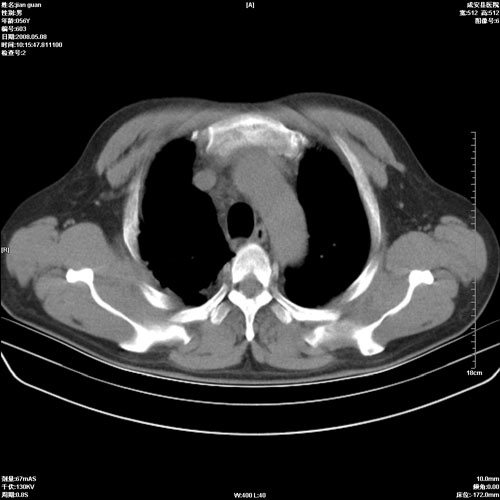

病人 男 60岁 主诉 胸闷 无明显发热 一般情况尚可。

考虑1心功不全,肺水肿

2右上肺结核纤维性病灶、肺气肿

2.心脏增大(以左心室增大为著),请结合b超及听诊.

2.肺门血管扩张,心脏增大,为肺心病

陈旧性肺结核,左心房扩大,左心衰竭

2右上肺结核纤维性病灶、肺气肿 ,肺心病